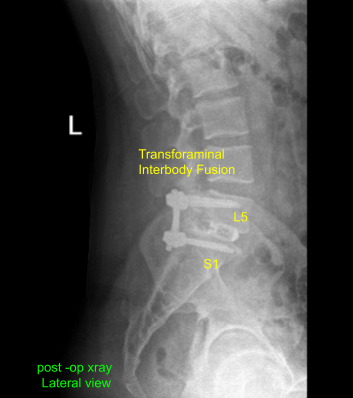

Case Study: Transforaminal Interbody fusion

with Pedicle screw fixation of L5-S1

A trial cage was inserted and checked under fluoroscopy and it was decided to put a 9 mm x 36 mm titanium cage. Allograft was used and mixed with morselized auto bone graft of the lamina and spinous process. The cage and disc interspace was filled with bone graft and the cage was inserted and checked under fluoroscopy, found to be in satisfactory position.

A thorough irrigation of the wound was done and decortication of the transverse process of both L5, sacral ala as well as parts on the right side was performed and bone graft was inserted over the Fibergraft. The 45-mm rods were used to connect the both pedicle screws on either side and the set screws were inserted and tightened and torqued.

Postoperative X Ray showed there is a normal lumbar lordosis. There were no destructive abnormalities or fractures. The intervertebral disc spaces appear preserved. There was no spondylolisthesis. The facet joints appear unremarkable.